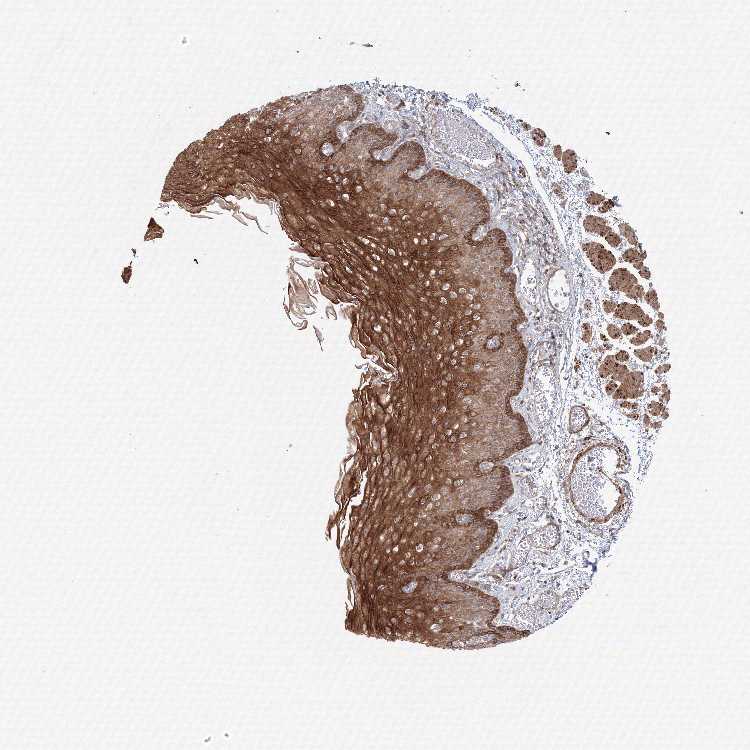

TISSUE PRIMARY DATA ESOPHAGUS Show tissue menu

ESOPHAGUS - Antibody stainingi

Antibody staining in the annotated cell types in the current human tissue is reported as not detected, low, medium, or high, based on conventional immunohistochemistry profiling in selected tissues. This score is based on the combination of the staining intensity and fraction of stained cells.

Each image is clickable and will lead to virtual microscopy that enables deeper exploration of all samples and also displays staining intensity scores, fraction scores and subcellular localization as well as patient and tissue information for each sample.

Antibody HPA037922Antibody HPA037923

Squamous epithelial cells MediumHigh